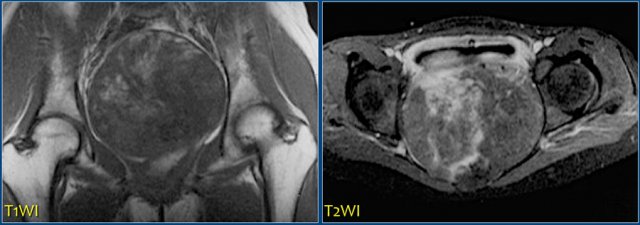

On the left a patient with a chondrosarcoma of the right acetabulum.

On the CT expansion and subtle calcifications are present.

On the coronal T2-weighted image the tumor is seen as a large lobulated mass with very high SI, which is typical for chondroid tumors.

The T1-weighted image after Gd shows typical peripheral nodular enhancement.

In the center there is no enhancement.

This is probably due to a large myxoid component. .